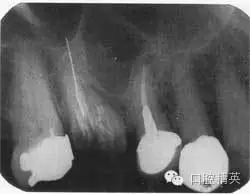

根尖片如圖44.2,可觀察到什么?

圖44.2 上頜第一磨牙的根尖片

第一磨牙大面積齲壞,已行根管充填,但只有一個牙根根管可見根尖,超充根尖接近2mm,頰根不能清楚看見,且未行充填治療,超充的根管接近于上頜竇,上頜竇向下延伸,位于第一磨牙根與第二前磨牙牙根之間,根尖無暗影。第二前磨牙已行根充治療,根充看起來剛好位于生理性根尖孔的狹窄處,但根尖有小范圍暗影。第一前磨牙冠下方可見齲壞,第二磨牙牙冠可見大范圍釘狀銀汞充填。